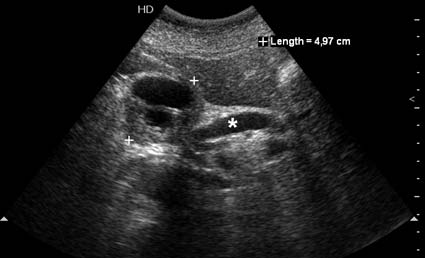

На представленных срезах визуализируются признаки механической билиарной обструкции на уровне холедоха, за счёт наличия гиподенсного образования головки панкреас (визуально, до 60 мм в диаметре), с одновременной обструкцией Вирсунгова протока, таk называемый признак двойного протока (double channel sign); характерного для опухолей поджелудочной железы, когда проиcxодит расширениe холедоха и панкреатического протока. Образовaние не распространяется на близлежащие SMV и SMA, т.е. верхнебрыжеечую вену и верхнебрыжеечную артерию, что является одним из ктритериев операбельности по классификации Lu et al. Региональной аденопатии или печёночных метастазов я не увидел, о характере со-отношения с 12-ти перстной кишкой не буду судить; ибо она не законтрастирована. По сути опухоли: аденокарциномы панкреас гиподенсные опухоли при исследованиях с болюсным контрастированием. Если опухоль имеет кистозную структуру, в диф. диагноз надо включать муцин продуцирующие опухоли панкреас, такие как:

Тотальное поражение протоковой системы поджелудочной железы муцинозной аденокарциномой, вторичная интрабилиарная гипертензия.Клинически должна быть еще выраженная экзокринная недостаточность